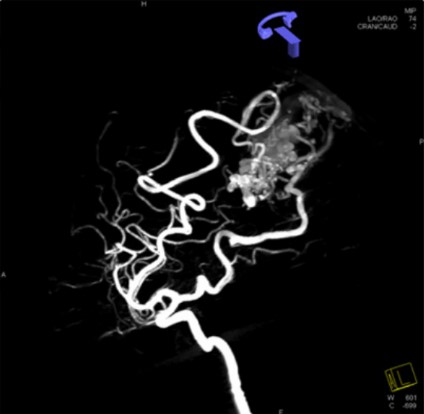

뇌 동정맥 기형

선천적인 발달 이상으로 동맥이 모세혈관을 거치지 않고 바로 정맥으로 연결되는 혈관의 기형이 생기는데 이것을 동정맥 기형이라고 부릅니다. 혈관이 풍부한 폐, 간, 비장 등의 장기에도 생기며 주로 뇌에 발생하여 뇌출혈이나 간질 발작과 같은 문제를 일으키는데, 이를 뇌동정맥 기형이라고 부릅니다.

코일색전술, Onyx 색전술